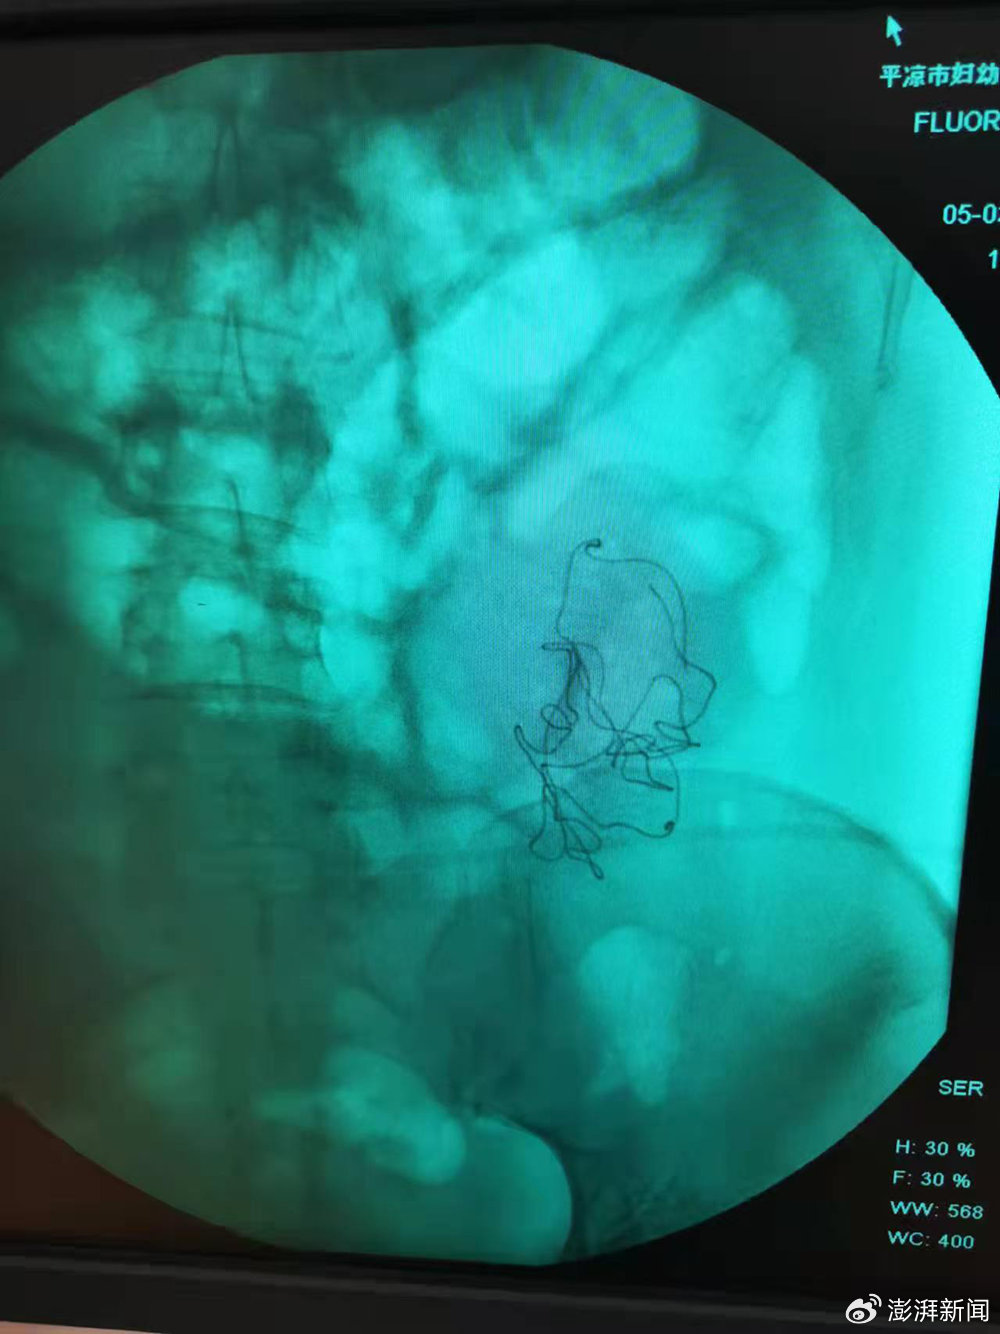

秦红利分娩后,进行X光检查发现异物清晰可见。澎湃新闻

早在2025年7月,当地卫健部门已查明,涉事医生干丽敏和尚蓝天伪造了秦红利病历中的手术记录和手术后病程记录——那些关于「X线透视显示有少量液平面」等记录,均是伪造。而那块曾在产房内被反复翻找、最终在X光影像中清晰可见的纱布,是否曾被遗留在秦红利体内,至今仍无一致解释。